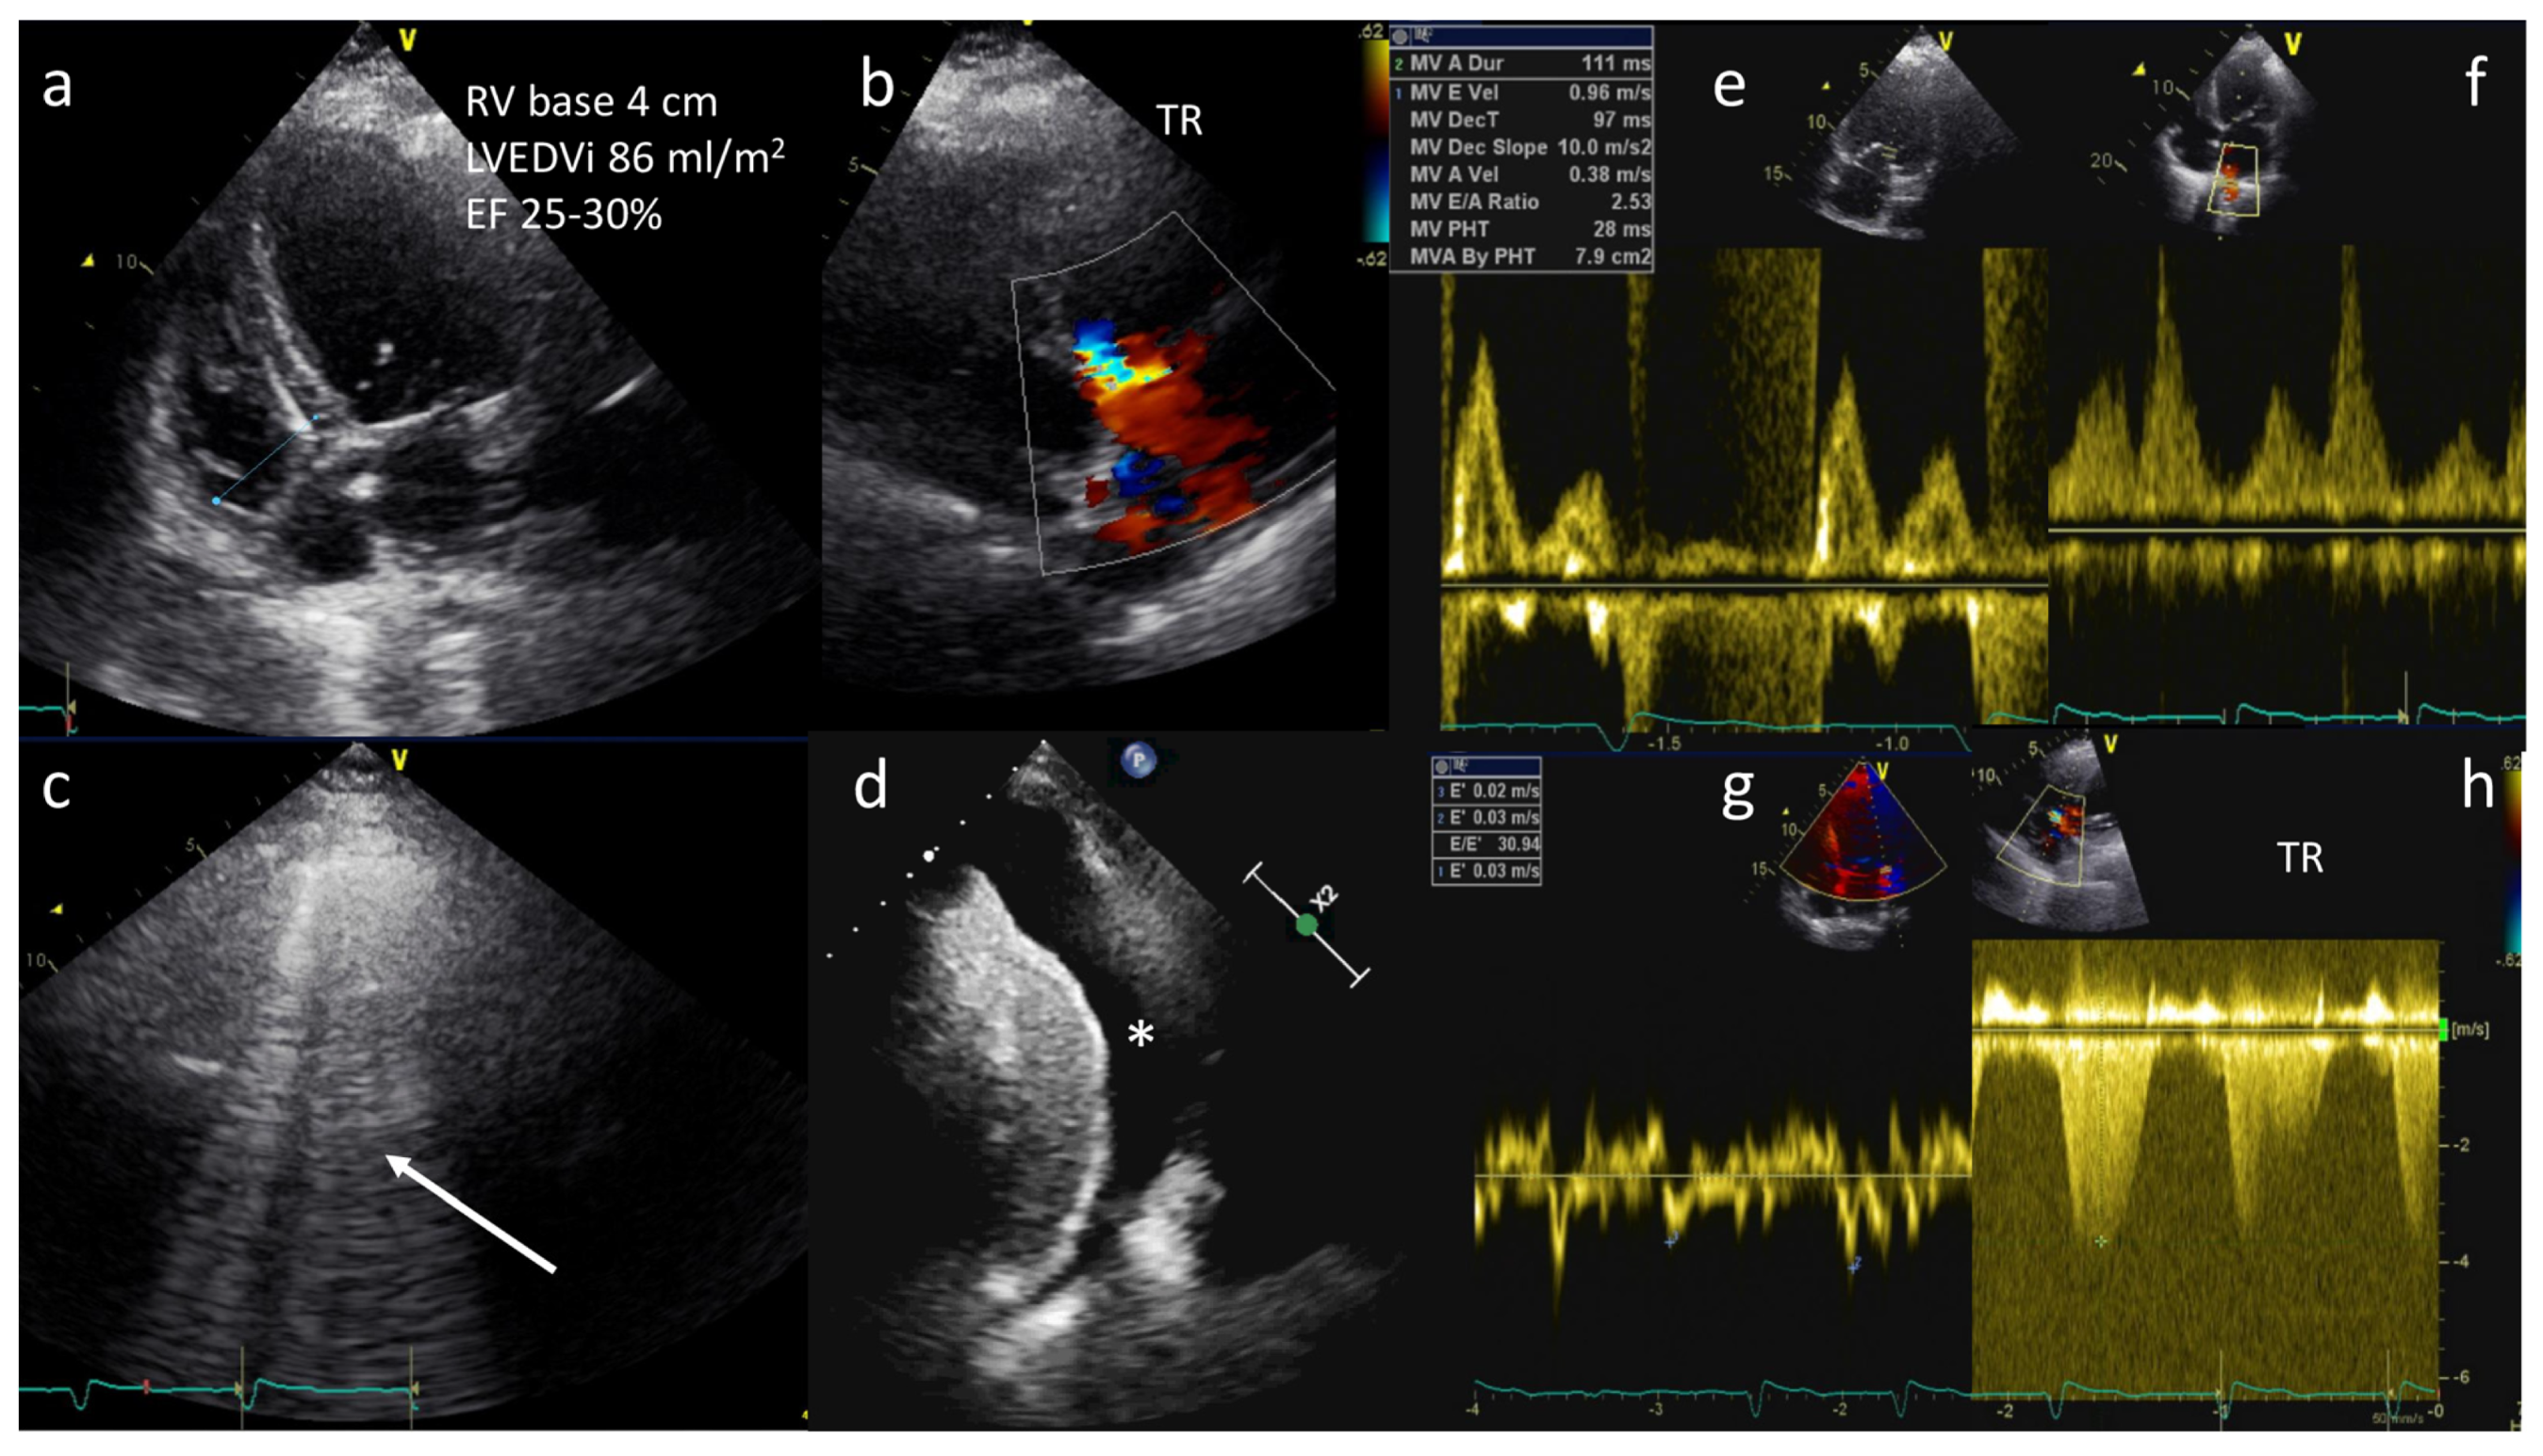

- Transthoracic echocardiography (TTE)